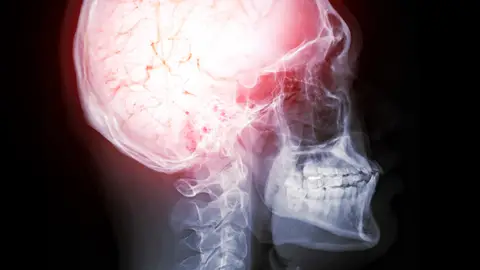

Con esto en mente, un reciente estudio publicado en Jama, analizó las conductas de casi 10.000 adolescentes ha identificado diferencias distintivas en las estructuras cerebrales de aquellos que consumieron sustancias antes de los 15 años en comparación con aquellos que no las consumieron. Muchas de estas diferencias estructurales cerebrales parecían existir en la infancia antes del consumo de cualquier sustancia, lo que sugiere que pueden desempeñar un papel en el riesgo de iniciar el consumo de sustancias más adelante en la vida, junto con factores genéticos, ambientales y otros factores neurológicos.

Ambas conductas se asociaron con una variedad de diferencias estructurales a nivel global del cerebro, así como con diferencias estructurales más específicas que involucraban principalmente la corteza. Si bien estos datos podrían algún día ayudar a informar las estrategias de prevención clínica, el equipo de Volkow enfatiza que la estructura cerebral por sí sola no puede predecir el consumo de sustancias durante la adolescencia, y que estos datos no deben usarse como una herramienta de diagnóstico.

El estudio analizó imágenes por resonancia magnética realizadas a 9.804 niños de todo Estados Unidos cuando tenían entre 9 y 11 años y siguieron a los participantes durante tres años para determinar si ciertos aspectos de la estructura cerebral capturados en las imágenes se vinculaban con el inicio temprano en el consumo de sustancias.

Luego, el equipo de Volkow, evaluó las diferencias tanto globales como regionales en la estructura cerebral, observando medidas como el volumen, el grosor, la profundidad de los pliegues cerebrales y la superficie, principalmente en la corteza cerebral. La corteza es la capa más externa del cerebro, densamente poblada de neuronas y responsable de muchos procesos de nivel superior, como el aprendizaje, la sensación, la memoria, el lenguaje, la emoción y la toma de decisiones.

Los resultados mostraron cinco diferencias estructurales cerebrales a nivel global entre quienes informaron haber consumido sustancias antes de los 15 años y quienes no lo hicieron. Estas diferencias incluían un mayor volumen cerebral total y un mayor volumen subcortical en quienes indicaron haber consumido sustancias. En total se identificaron otras 39 diferencias estructurales cerebrales a nivel regional. Lo sorprendente es que algunas de ellas también parecían exclusivas del tipo de sustancia consumida.